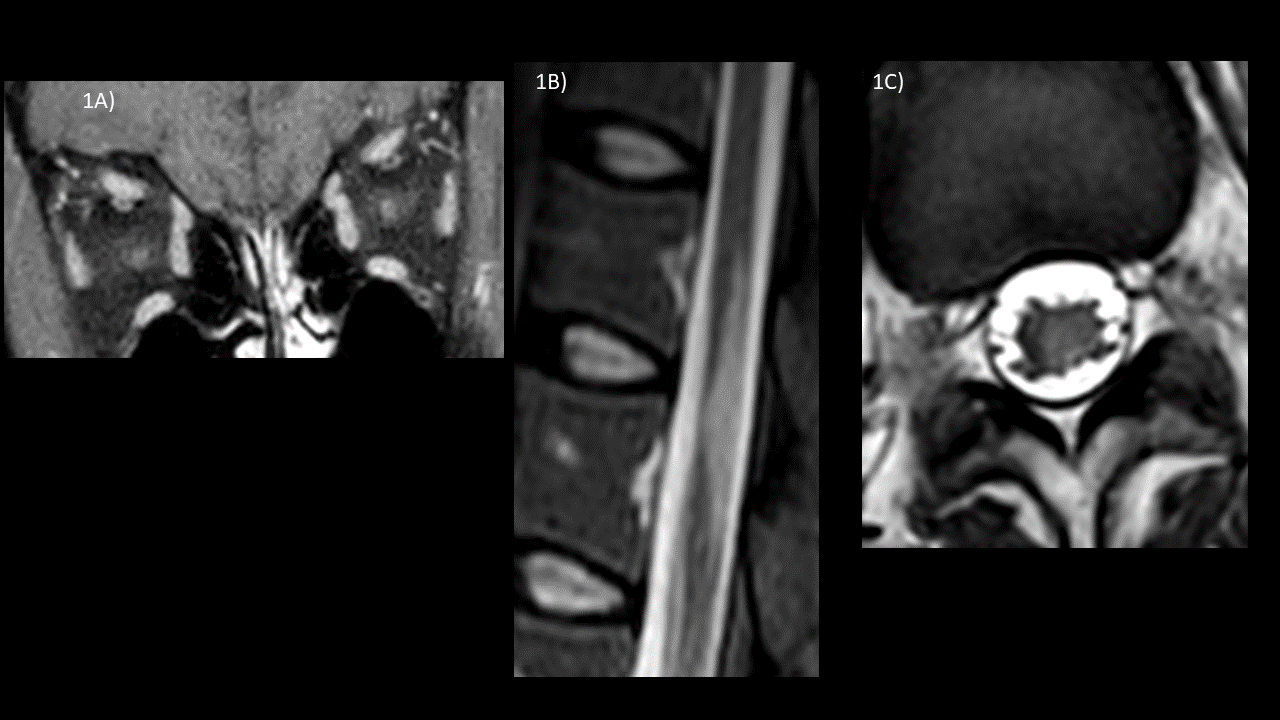

2A-B) Cortes axiales en ponderación FLAIR, mostrando zonas hiperintensas en la parte medial del tálamo izquierdo y  en la superficie periependimaria del tercer ventrículo, evocando igualmente lesiones desmielinizantes.

2C) Corte coronal ponderado FLAIR que muestra la distribución peripendimaria en torno al tercer ventrículo y la anomalie de senal talamique izquierda.

– cerebral: los pacientes con AQP4-IgG positivo suelen tener lesiones hiperintensas en FLAIR en periventricular y afectación de los tractos corticoespinales . Los pacientes con MOG-IgG-positivo con mayor frecuencia tienen lesiones desmielinizantes en los ganglios de la base, tálamo o lesiones infratentoriales.